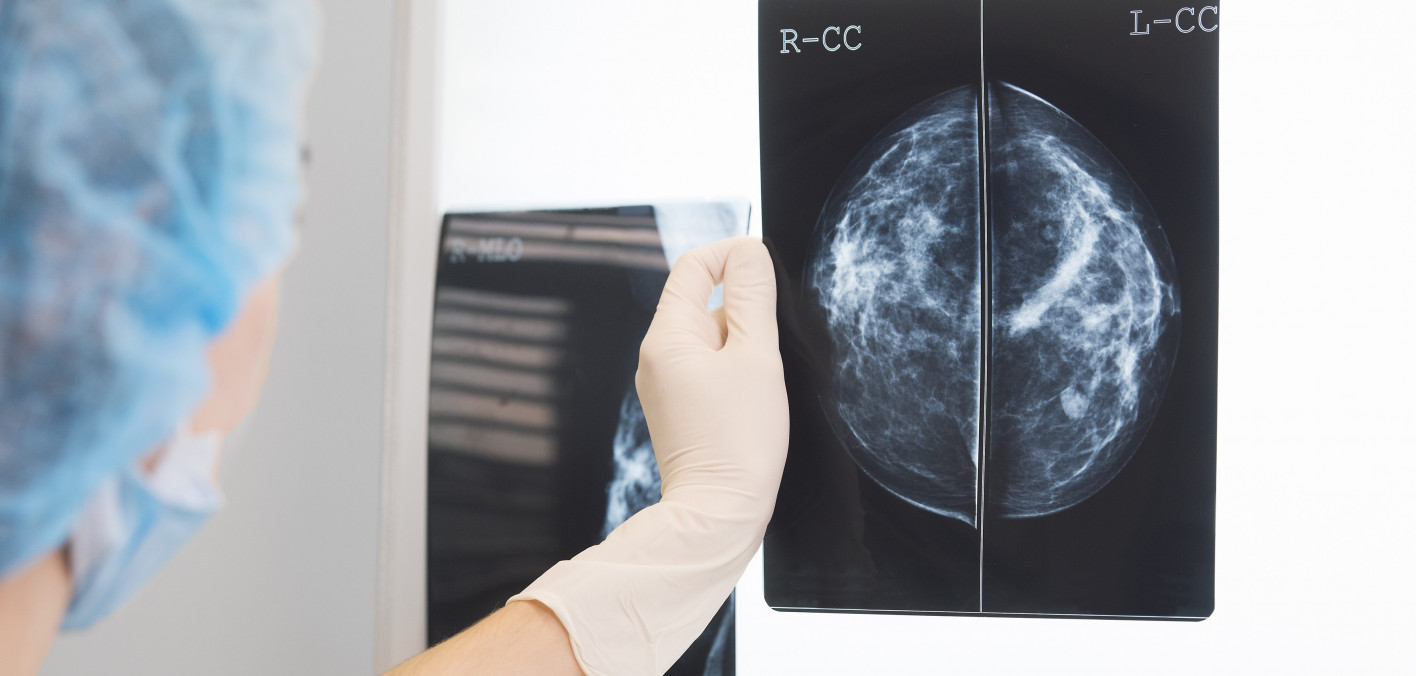

How Often Are Breast Biopsies Cancer . The removed cells are examined under a microscope and further tested. A breast biopsy is a test that removes tissue or sometimes fluid from the suspicious area. But how often does a breast biopsy come back positive for breast cancer diagnosis?. A biopsy is the only way to determine whether a breast lump is noncancerous (benign) or cancerous (malignant). A breast biopsy is a test that examines a sample of tissue to determine if it is cancerous. A core needle biopsy (cnb) uses a larger hollow needle to sample breast changes felt by the doctor or seen on an. What percentage of breast biopsies are cancer? A breast biopsy might be recommended if you have a suspicious area in your breast, such as a breast lump or other signs and symptoms of breast cancer. Over one million people have breast biopsies each year in the united states. After thorough analysis, a pathologist (a. For women aged 40 to 49 years, 20% of breast biopsies showed breast cancer. For women age 50 to 59 years old, 32% of biopsies were positive for cancer.

A biopsy is the only way to determine whether a breast lump is noncancerous (benign) or cancerous (malignant). The removed cells are examined under a microscope and further tested. Over one million people have breast biopsies each year in the united states. A breast biopsy might be recommended if you have a suspicious area in your breast, such as a breast lump or other signs and symptoms of breast cancer. A breast biopsy is a test that examines a sample of tissue to determine if it is cancerous. For women aged 40 to 49 years, 20% of breast biopsies showed breast cancer. A core needle biopsy (cnb) uses a larger hollow needle to sample breast changes felt by the doctor or seen on an. What percentage of breast biopsies are cancer? After thorough analysis, a pathologist (a. For women age 50 to 59 years old, 32% of biopsies were positive for cancer.

How Often Are Breast Biopsies Cancer For women age 50 to 59 years old, 32% of biopsies were positive for cancer. A breast biopsy is a test that examines a sample of tissue to determine if it is cancerous. A core needle biopsy (cnb) uses a larger hollow needle to sample breast changes felt by the doctor or seen on an. What percentage of breast biopsies are cancer? The removed cells are examined under a microscope and further tested. For women aged 40 to 49 years, 20% of breast biopsies showed breast cancer. A breast biopsy is a test that removes tissue or sometimes fluid from the suspicious area. But how often does a breast biopsy come back positive for breast cancer diagnosis?. For women age 50 to 59 years old, 32% of biopsies were positive for cancer. Over one million people have breast biopsies each year in the united states. A biopsy is the only way to determine whether a breast lump is noncancerous (benign) or cancerous (malignant). After thorough analysis, a pathologist (a. A breast biopsy might be recommended if you have a suspicious area in your breast, such as a breast lump or other signs and symptoms of breast cancer.